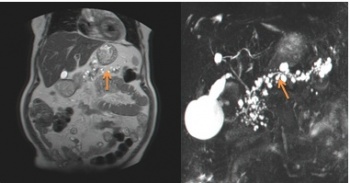

- טומוגרפיה ממוחשבת (CT) : בטומוגפיה ממוחשבת אפשר לראות היטב את הלבלב והנגעים בו פחות טוב נראה את מערכת הצינורות (תצלום 28.9)

- צילום דרכי מרה בעזרת תהודה מגנטית (Magnetic resonance cholangiopancreatography - MRCP): בדיקה זו היא הרגישה מבין הבדיקות לזיהוי נגעים בלבלב ובצינורות הלבלב. מאז הוכנסה לשימוש חל שיפור משמעותי ביכולת האבחון של נגעים בלבלב.